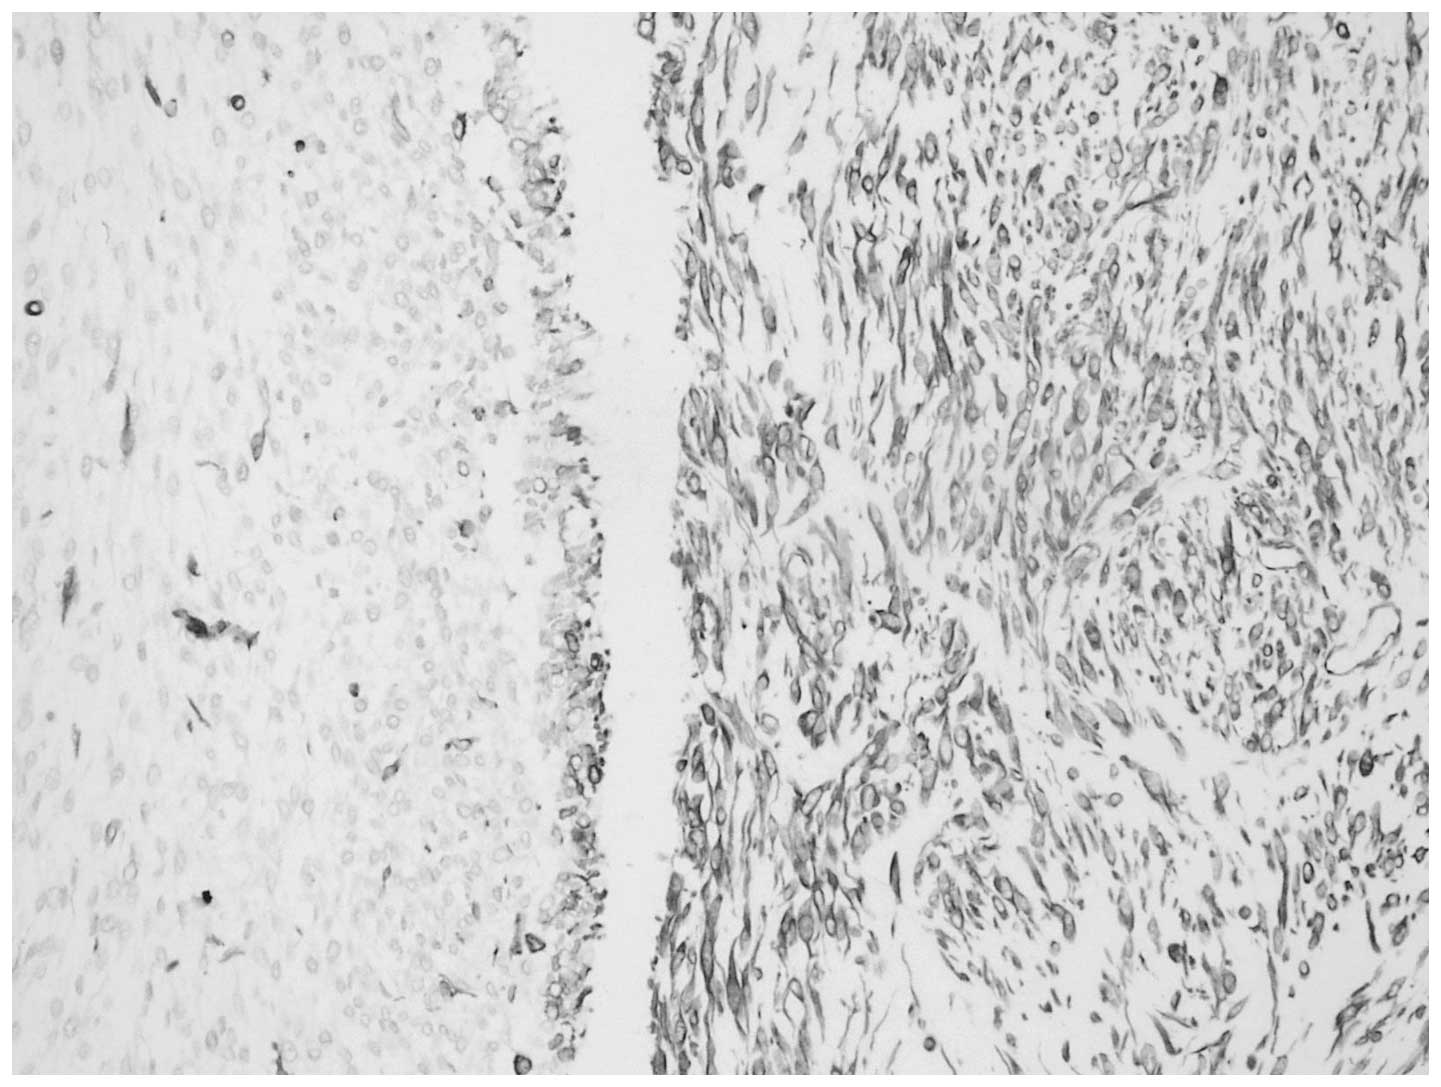

Macroscopic examination of the 13×8×6-cm nephrectomy specimen revealed a 8×5×4-cm tumoral mass in the renal pelvis. The cut section of the mass was gray-white in color, with a hard consistency. Areas of extensive necrosis were also present. The tumor had invaded the full-thickness of the renal pelvic wall and peripelvic adipose tissue. Furthermore, invasion into the renal parenchyma was observed. Histological examination of the tumor showed a malignant neoplasm comprising of epithelial and mesenchymal components, which were largely separated from each other (Fig. 2). However, in certain areas, the epithelial component blended into the sarcomatous component, generating a histological transition between the two. The sarcomatous areas primarily consisted of spindle cells, which were full of eosinophilic cytoplasm. Immunohistochemical staining was performed using a panel of markers, including cytokeratin, vimentin, Ki-67 antigen and p53. The epithelial portion of the tumor was found to stain positively for cytokeratin (Fig. 3) and the sarcomatoid spindle cells were observed to stain positively for vimentin, but negatively for cytokeratin (Fig. 4). The tumor cells in the epithelial and sarcomatous components were also found to express p53 protein in the nuclei. The expression level of p53 was >10%. Furthermore, the Ki-67 labeling indices were >20% in all of the tumor cells. Due to the advanced age of the patient, chemotherapy and radiotherapy were not administered. The patient was discharged six days after surgery and no recurrence was observed after eight months.

Figure 4

Immunohistochemical staining showing immunoreactivity for vimentin in the spindle cells of the carcinosarcoma. Magnification, ×20.

Due to the similar microscopic appearance of carcinosarcomas and sarcomatoid carcinomas, immunohistochemistry may be a useful diagnostic adjunct for differentiating between these tumors. In the present case, antigenic determinants that were specific for epithelial cells, such as cytokeratin, were identified. Furthermore, the sarcomatous component was characterized by strong staining for vimentin. In addition, the lack of expression of keratin markers in the mesenchymal component further confirmed the diagnosis of carcinosarcoma.